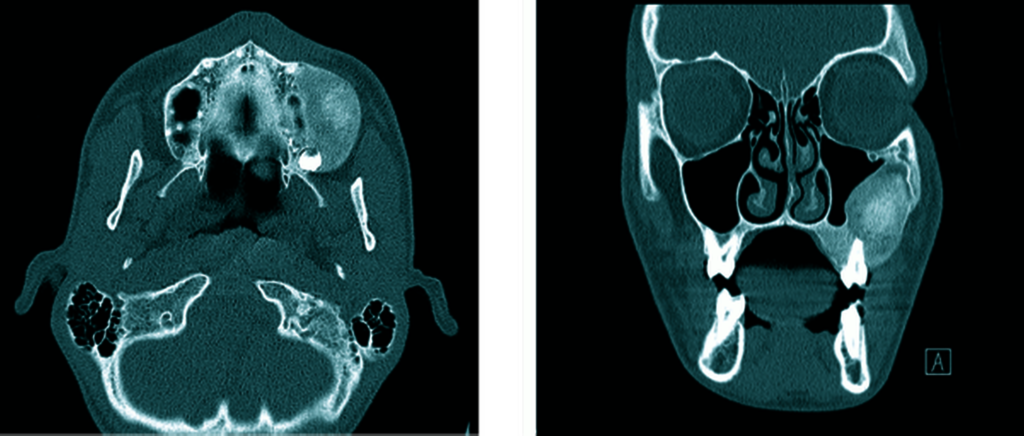

Die zur weiteren dreidimensionalen Ausbreitungsdiagnostik, einschließlich des Bezugs zur Orbita, sowie zur Beurteilung des extrakraniellen knöchernen Verlaufs des zweiten Trigeminusastes und des Canalis opticus durchgeführte native Computertomografie (CT) des Gesichtsschädels (Abbildung 3) zeigte eine homogene und scharf begrenzte ossäre Raumforderung der linken Maxilla mit milchglasartiger Matrix unter Beteiligung des Processus alveolaris, des Processus zygomaticus und der lateralen Kieferhöhlenwand sowie einer Beteiligung der kaudolateralen Anteile des Orbitabodens und einer geringen Auftreibung der rostralen Anteile des Canalis infraorbitalis. Konsekutiv war der Sinus maxillaris bei regelrechter Belüftung von lateral pelottiert. Die Orbita zeigte ansonsten eine symmetrische Darstellung einschließlich der retrobulbären Strukturen und des Canalis opticus ohne CT-grafisch erkennbaren Exophthalmus. Die Läsion zeigte weder eine Kortikalisdestruktion noch eine Periostreaktion oder eine suspekte Weichteilkomponente. Die augenärztliche Untersuchung blieb ohne weiteren pathologischen Befund. Die Zusammenschau der bildgebenden und der klinischen Befunde führte zur Arbeitsdiagnose einer fibrösen Dysplasie der Maxilla.